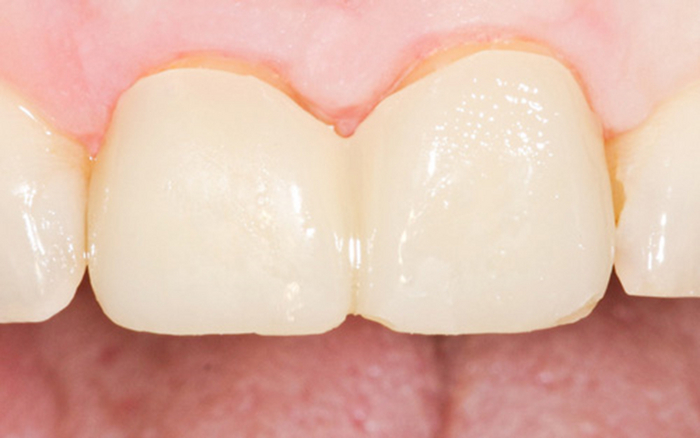

4 . Коронка из прессованной керамики.

Она же стеклокерамика, она же «E-Max», «Имакс»(В честь распространенного бренда керамики), ПК.

Делают из дисиликата лития методом прессования или фрезеровки.

Плюсы:

-точнейшая анатомия и прилегание

-шикарная эстетика. Из этой керамики делают ещё и виниры. Можно всячески красить, индивидуализировать, играться с прозрачностью

-долгий срок службы

-нет потемнения десны

-можно делать на имплантатах

Вывод: если хочется красиво и качественно, то твой вариант, но надо смотреть на детали. Если к зубам пофигистичное отношение, то лучше рассмотри что-то другое.